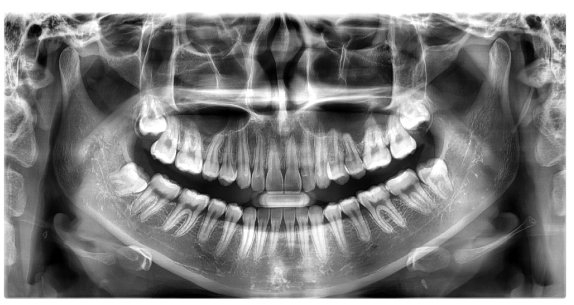

교정치료는 눈으로만 확인하고 정밀한 치료계획을 세울 수 없습니다.

구강 전반 및 얼굴뼈 부위까지 광범위한 진단을 통해 육안으로는 파악하기 어려운 부분까지 살펴볼 수 있습니다.

약2년간 이어지는 치료과정동안 의료진의 판단에 도움을 주어 올바른 치료가 될 수 있도록 도와주는 장비입니다.